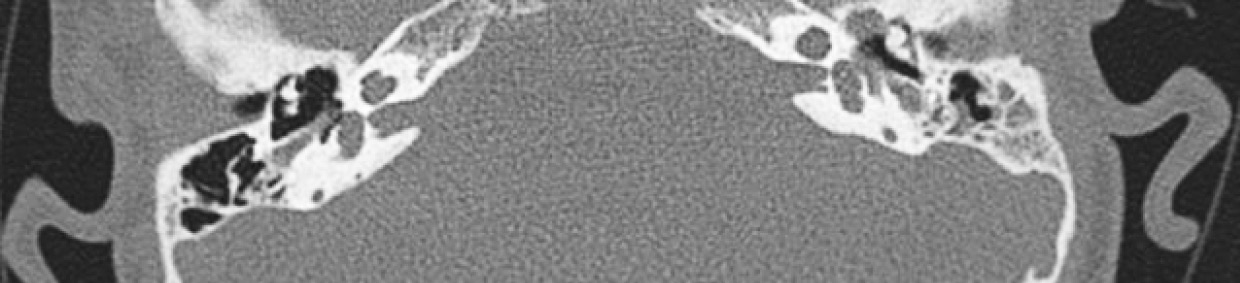

При проведении мультиспиральной компьютерной томографии височных костей в 2020 г. выявлены признаки двустороннего врожденного порока развития внутреннего уха — неполное разделение улитки 2 типа (рис. 2).

Рис. 2. Компьютерная томограмма височных костей в аксиальной проекции пациента — неполное разделение улитки 2-го типа

Fig. 2. Computed tomogram of the temporal bones in the axial projection of the patient — incomplete division of the cochlea type 2